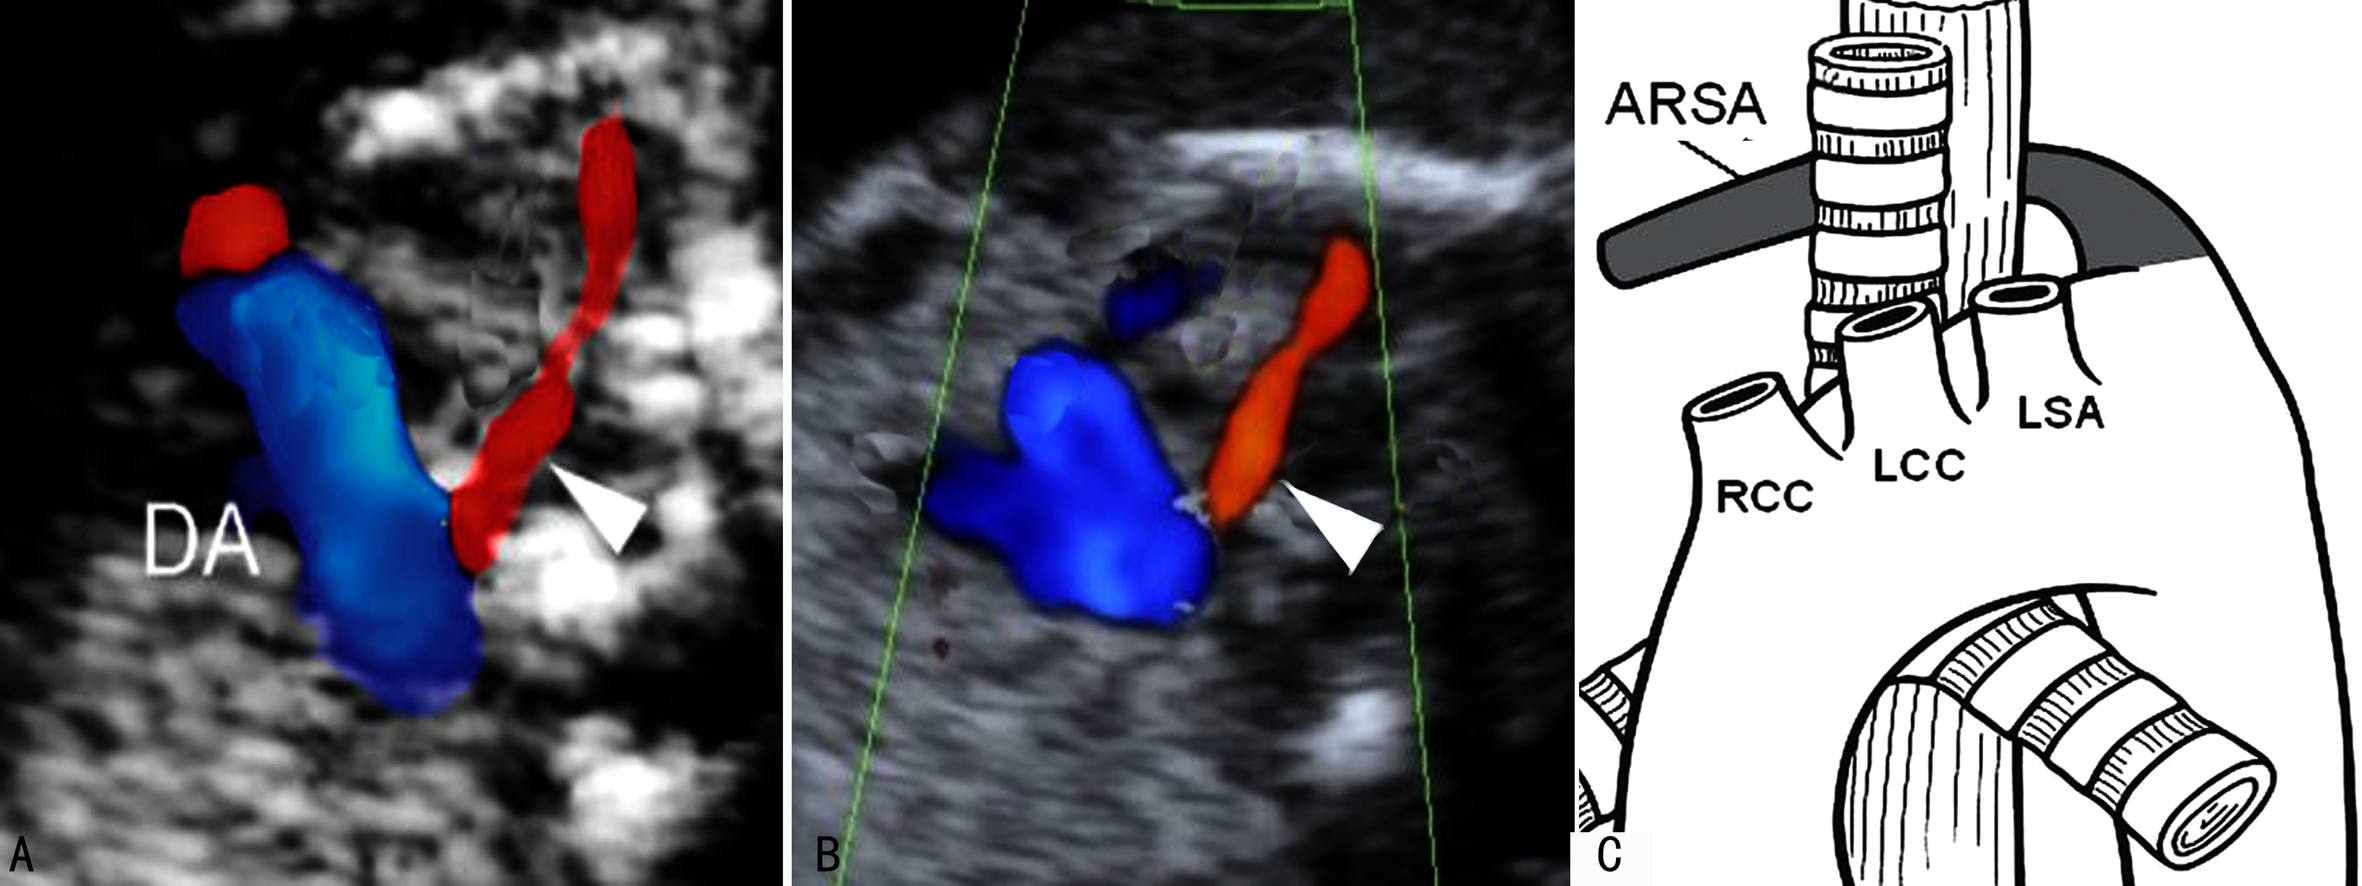

迷走右锁骨下动脉(aberrant right subclavian artery, ARSA)形成及解剖特点见前述(图5)。

对于中期妊娠中右锁骨下动脉迷走在21-三体综合征的发生情况,Paladini和De León-Luis等做了大量的观察和研究。De León-Luis等在统计了8781例胎儿(平均孕龄24 ± 5.4周)资料后发现,迷走右锁骨下动脉的发生率大约为1%,在7例非整倍体胎儿中,除迷走右锁骨下动脉外均发现合并其他异常;在Paladini等的资料中,21-三体综合征的胎儿迷走右锁骨下动脉的发生率为25%。

图5右侧锁骨下动脉迷走(三角箭头)